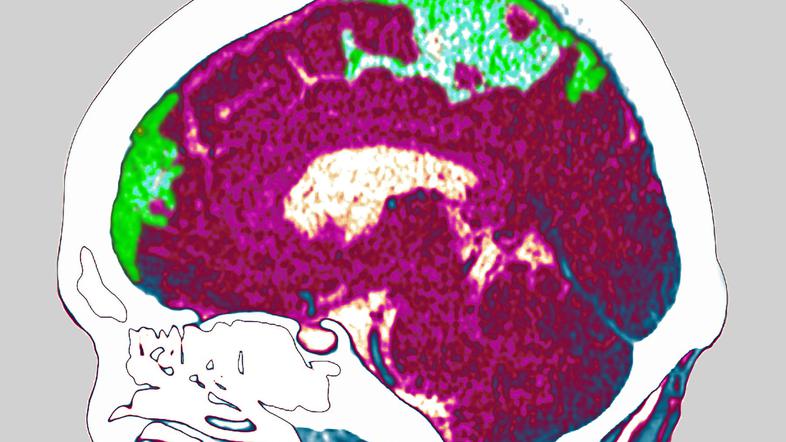

Možganska kap: "Na vrsti sem bil"

Možganska kap pri nas letno prizadene več kot 4000 ljudi oziroma več kot deset vsak dan.

Možganska kap je zelo težko stanje, saj v prvem mesecu po njej umre petina bolnikov, v letu dni še dodatna petina, visok odstotek pa jih trpi zaradi velike in trajne oviranosti.

Franca iz Dovij pri Mojstrani je možganska kap, ki jo je doživel pred letom dni, priklenila na voziček. "Center za hojo je bil zalit s krvjo in v možganih ni več prave komande," nam je pojasnil na rehabilitaciji, ob "ponovnem učenju hoje". "Nočem obstati na vozičku ali obležati v postelji. To ni življenje, še posebej zame ne, ki sem že vse življenje v športu," nam je zaupal ta, pred boleznijo zelo aktivni gospod; smučar, odbojkar, hribolazec. "K sreči sem bil v dobri kondiciji, sicer bi vse šlo k vragu. Teden prej sem smučal s skupino pod Mont Blancom, pred tem še v Italiji. Med tem sem šel v Ljubljano, kjer s kolegi že več kot 30 let igramo odbojko. Seveda sem zdravnike spraševal, ali sem bil mogoče preveč aktiven. Povedali so mi, da ni povezave. Pač, na vrsti sem bil," je še dodal.

Možganska kap je še vedno v porastu. Stroka ugotavlja, da na udaru niso samo starejši, kar ugotavlja tudi globalna študija iz leta 2013, ki je bila objavljena v ugledni medicinski reviji Lancet

Možganska kap pri nas letno prizadene več kot 4000 ljudi oziroma več kot deset vsak dan. Okoli 30 odstotkov ljudi jo utrpi v aktivnem delovnem obdobju.